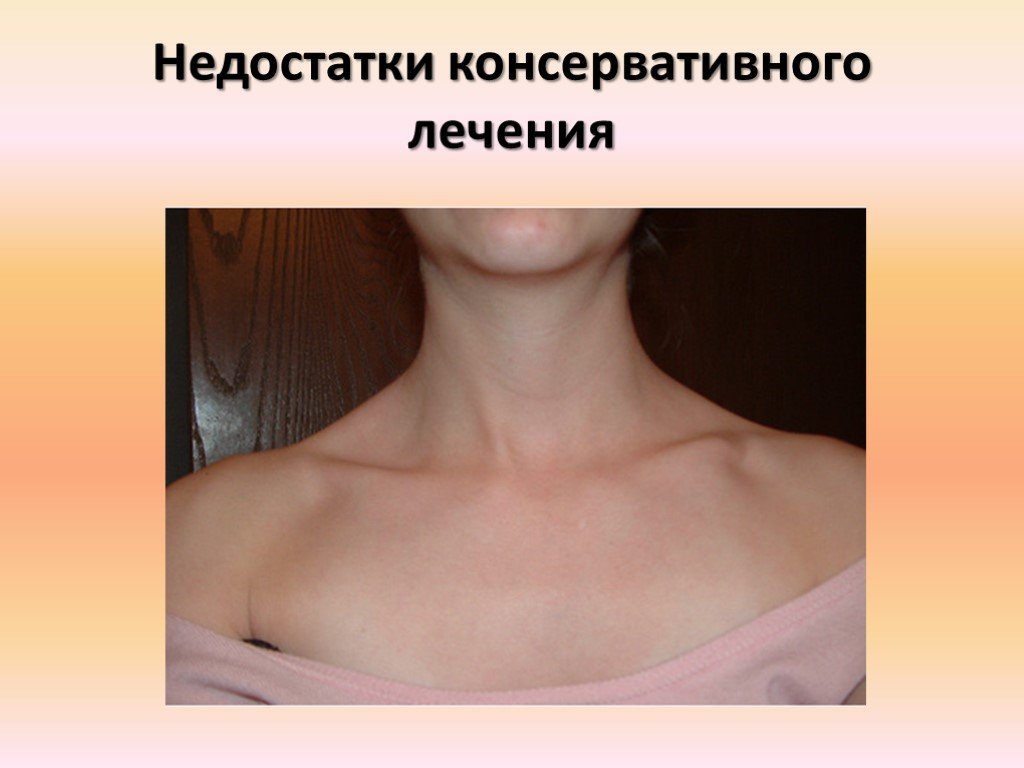

Вывихи и переломы ключицы презентация - 85 фото